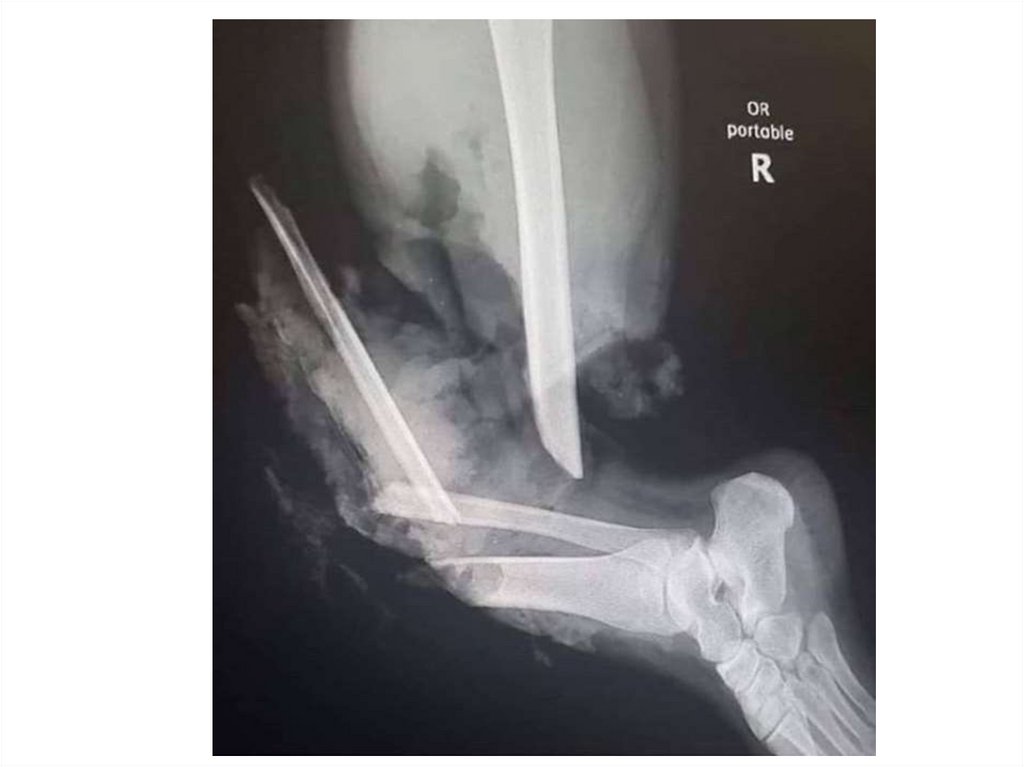

Назовите

• Вид исследования

• Область исследования

• Патологию